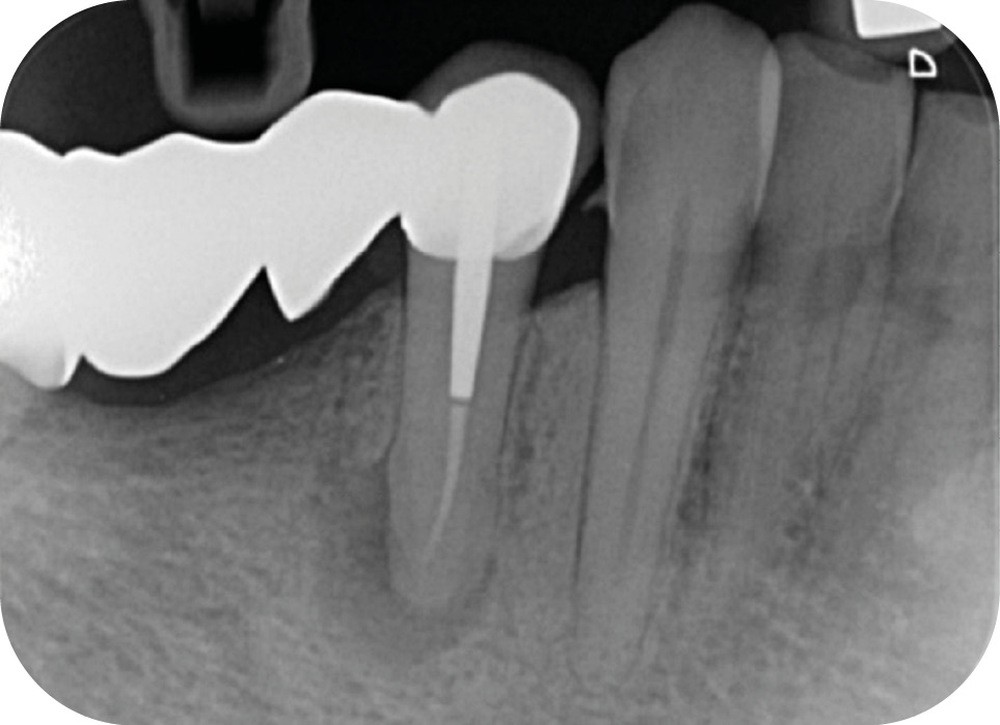

La cavité d’accès endodontique était alors traditionnellement réalisée en se figurant les axes de la racine et du bridge (fig. 2). Cette aptitude à s’orienter dans l’espace n’est cependant pas aisée, et différents outils numériques offrent aujourd’hui la possibilité de dessiner la trajectoire suspectée du canal sur les coupes de l’examen Cone Beam et d’aider le praticien à planifier son futur geste thérapeutique (fig. 3, 4). Après pose du champ opératoire, une voie d’accès est ainsi réalisée à travers le bridge en reportant les mesures de la planification 3D (fig. 5). Le tenon est déposé par vibration avec un insert ultrasonore puis la lecture des teintes dentinaires sous microscope permet d’objectiver la présence d’un canal supplémentaire non traité (fig. 6). Les surplombs dentinaires sont supprimés avec un insert ET18D (Actéon) et les entrées canalaires relocalisées avec une lime rotative d’évasement coronaire.

La mise en forme canalaire à travers un bridge impose des contraintes instrumentales importantes, et nécessite une analyse préopératoire minutieuse. Ici, nous avons eu recours à des limes de pré-élargissement mécanisé afin de sécuriser la trajectoire canalaire (fig. 7). Une préparation corono-apicale jusqu’à une finition apicale 25-6 % a ensuite été choisie afin d’optimiser le flux d’irrigant dans le tiers apical. À la suite de l’ajustage des maîtres cônes et d’un protocole d’irrigation finale (EDTA & NaOCl), une obturation selon la technique de condensation verticale à chaud est réalisée, puis la patiente est revue pour une restauration composite de la face occlusale (fig. 8, 9). Le contrôle à six mois révèle la disparition de la symptomatologie ainsi que des signes radiologiques de cicatrisation apicale (fig. 10).